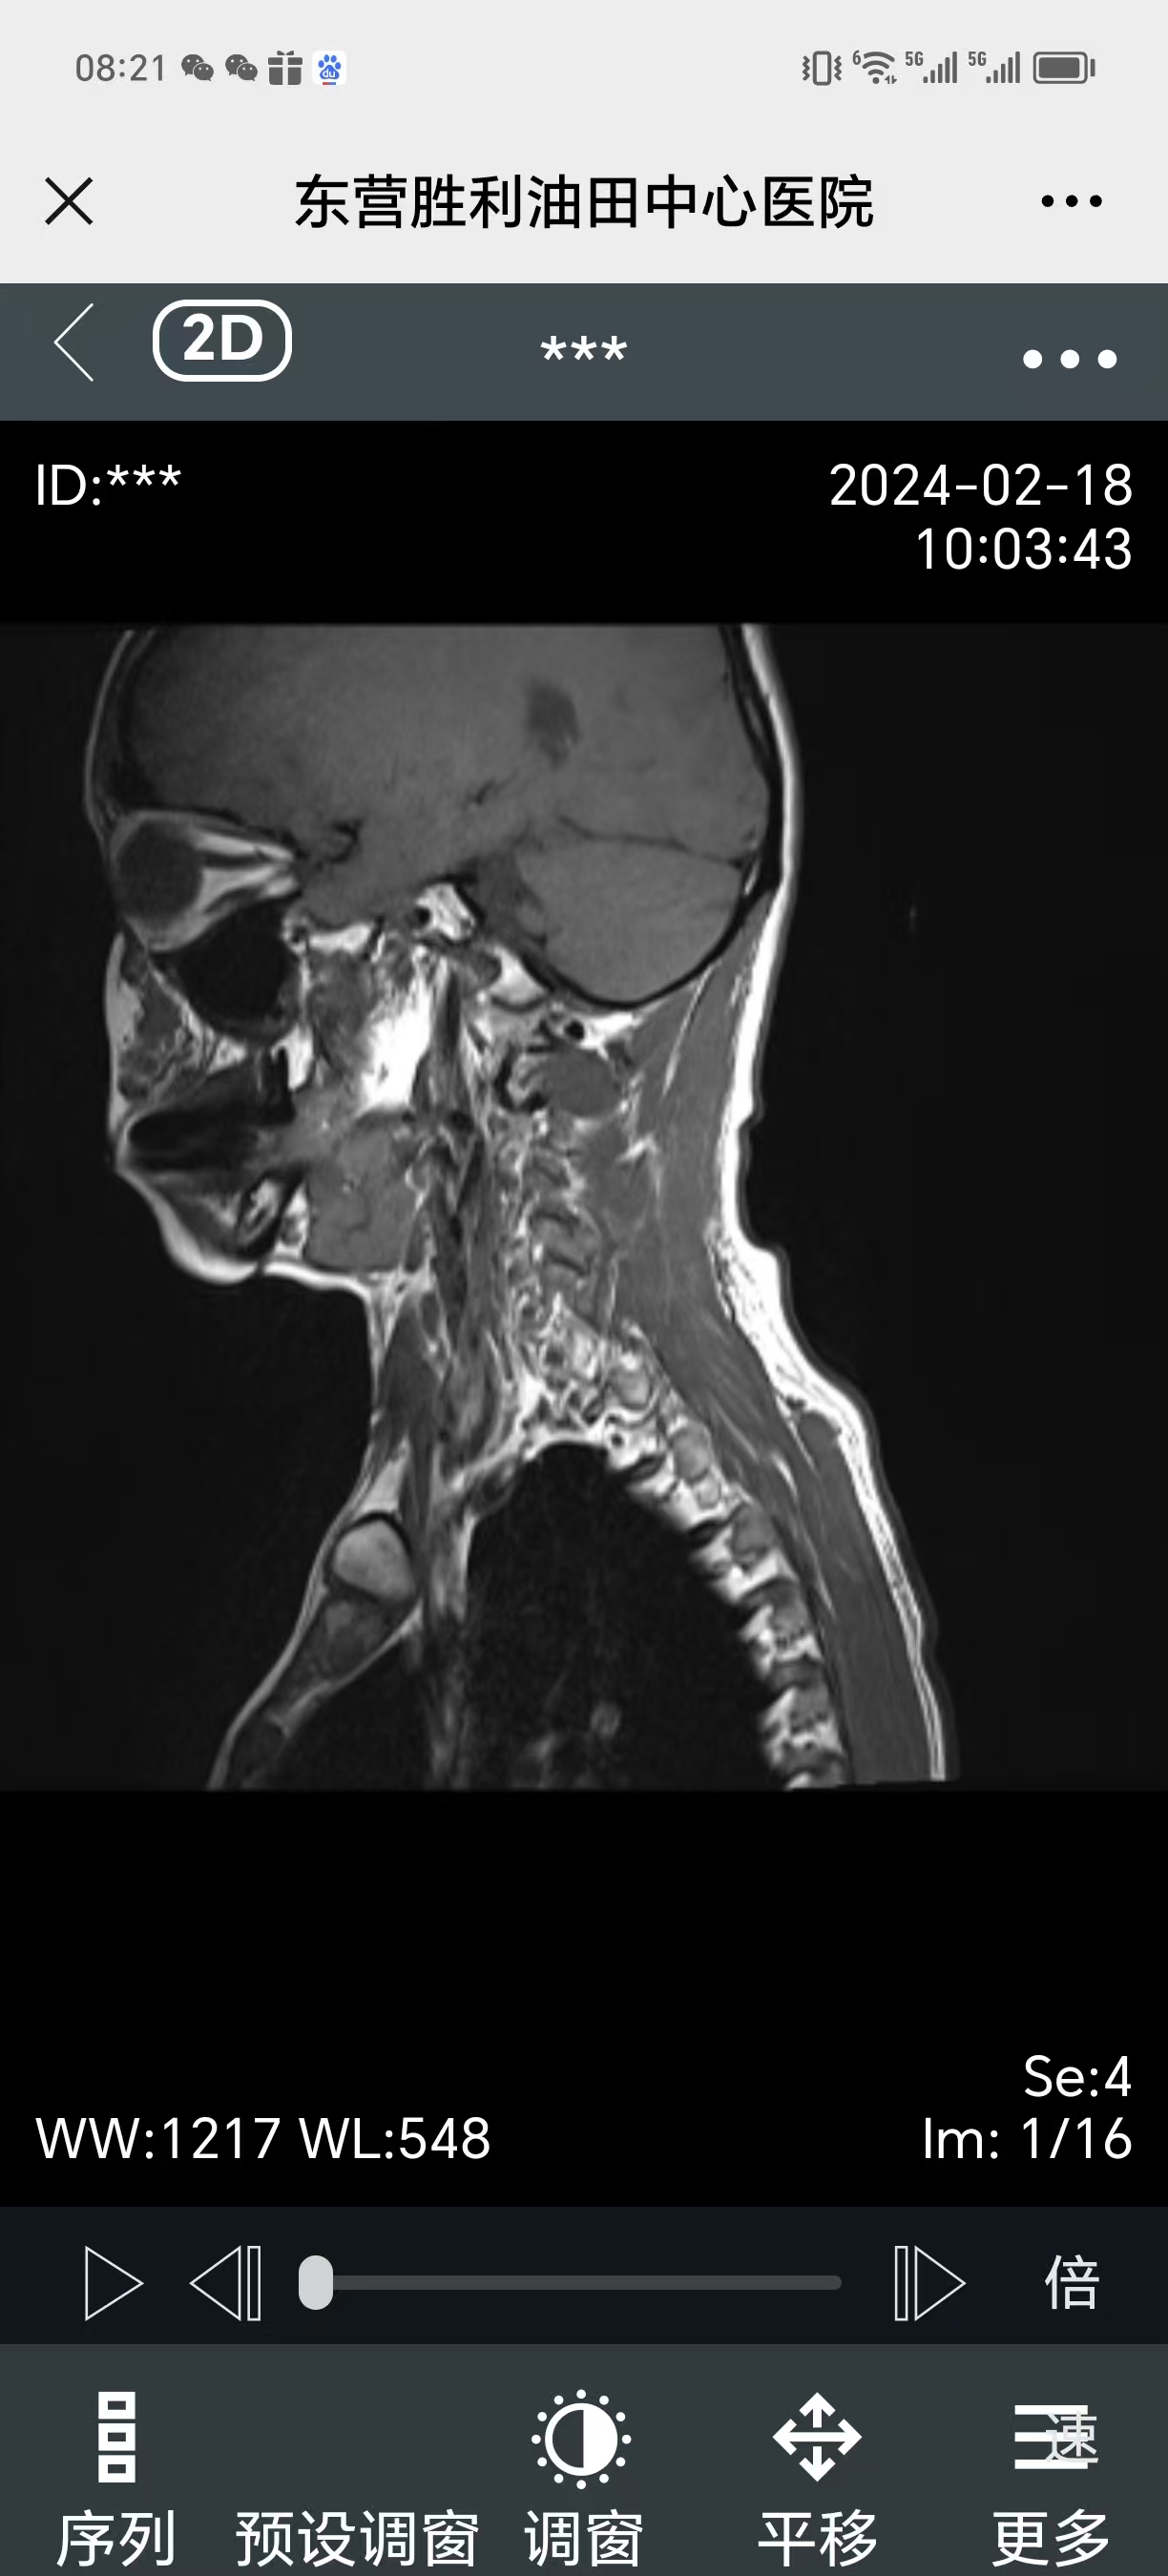

• 2024.02.18,复查,症状还在。